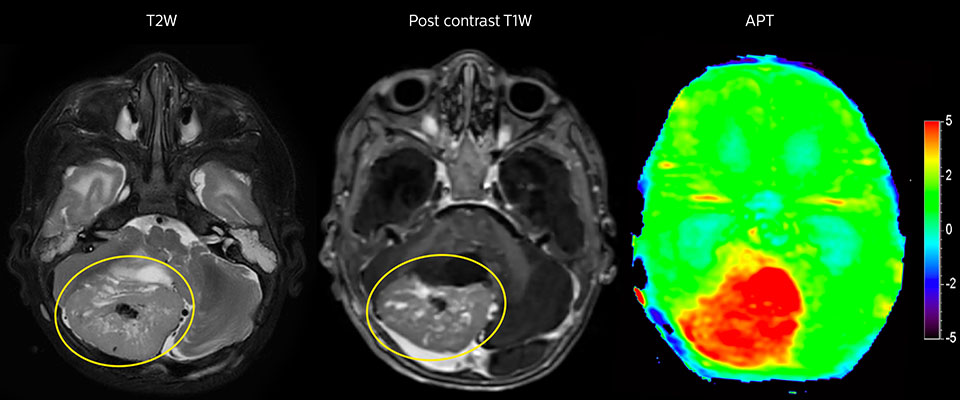

APT-Bildgebung eines hoch differenzierten Tumors

Tumorauswertung bei einem 1-jährigen Kind mit Medulloblastom. Dieser aggressive Tumortyp ist sehr solide und homogen. Das hohe APT-Signal entspricht dem kontrastverstärkten Bild dieses hoch differenzierten Tumors.